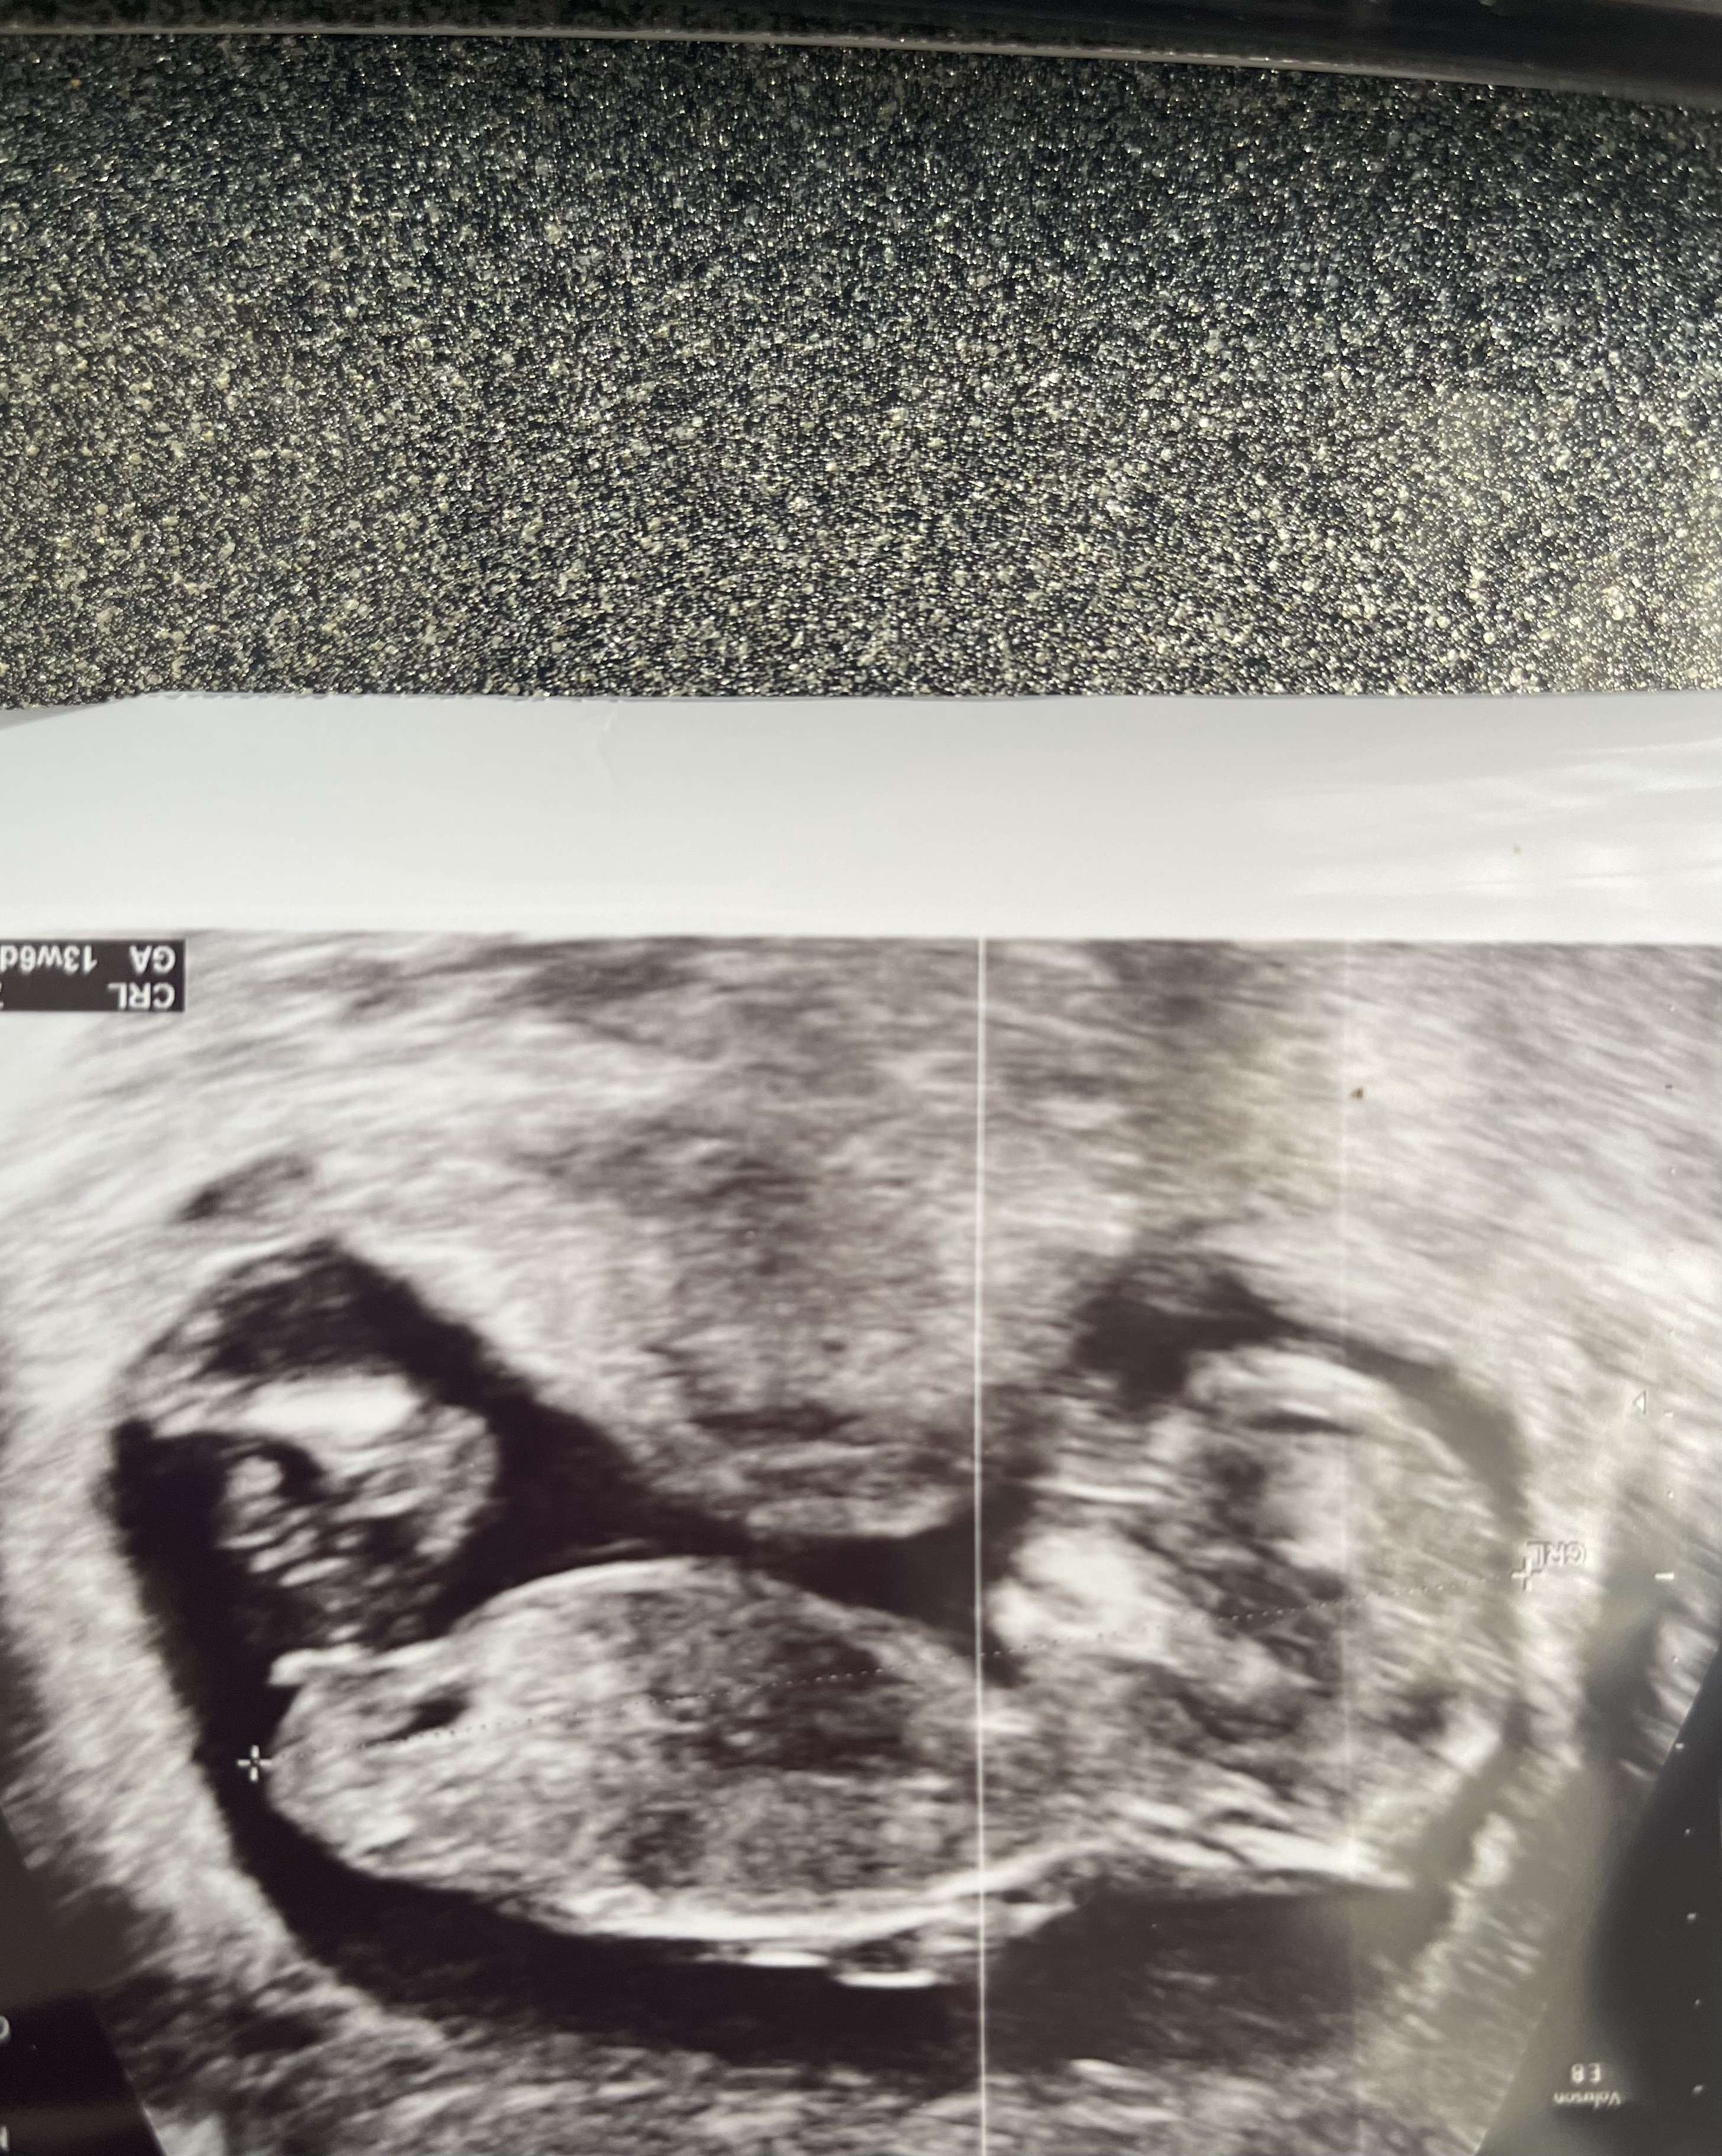

Na ostatniej wizycie ginekolog zasugerował płeć na podstawie wyrostka płciowego. Oczywiście zaznaczył, że nie jest to na 100%, ale wstępnie widzi dziewczynkę

Czy Wy też to widzicie?

Czy u którejś z Was był taki przypadek, że wyrostek też był poziomy względem kręgosłupa (dziewczynka), a już na kolejnych badaniach odstawał do góry i był jednak chłopiec?